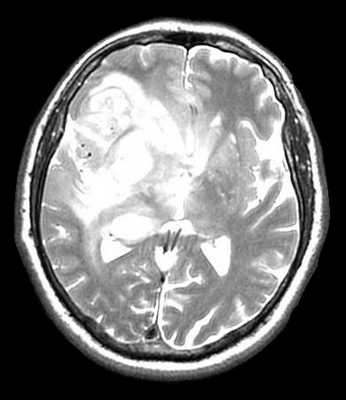

МРТ головного мозга. Глиобластома с поражением обеих лобных долей и височной доли справа. Аксиальные Т2-зависимая МРТ и FLAIR МРТ, сагиттальная Т1-зависимая МРТ.